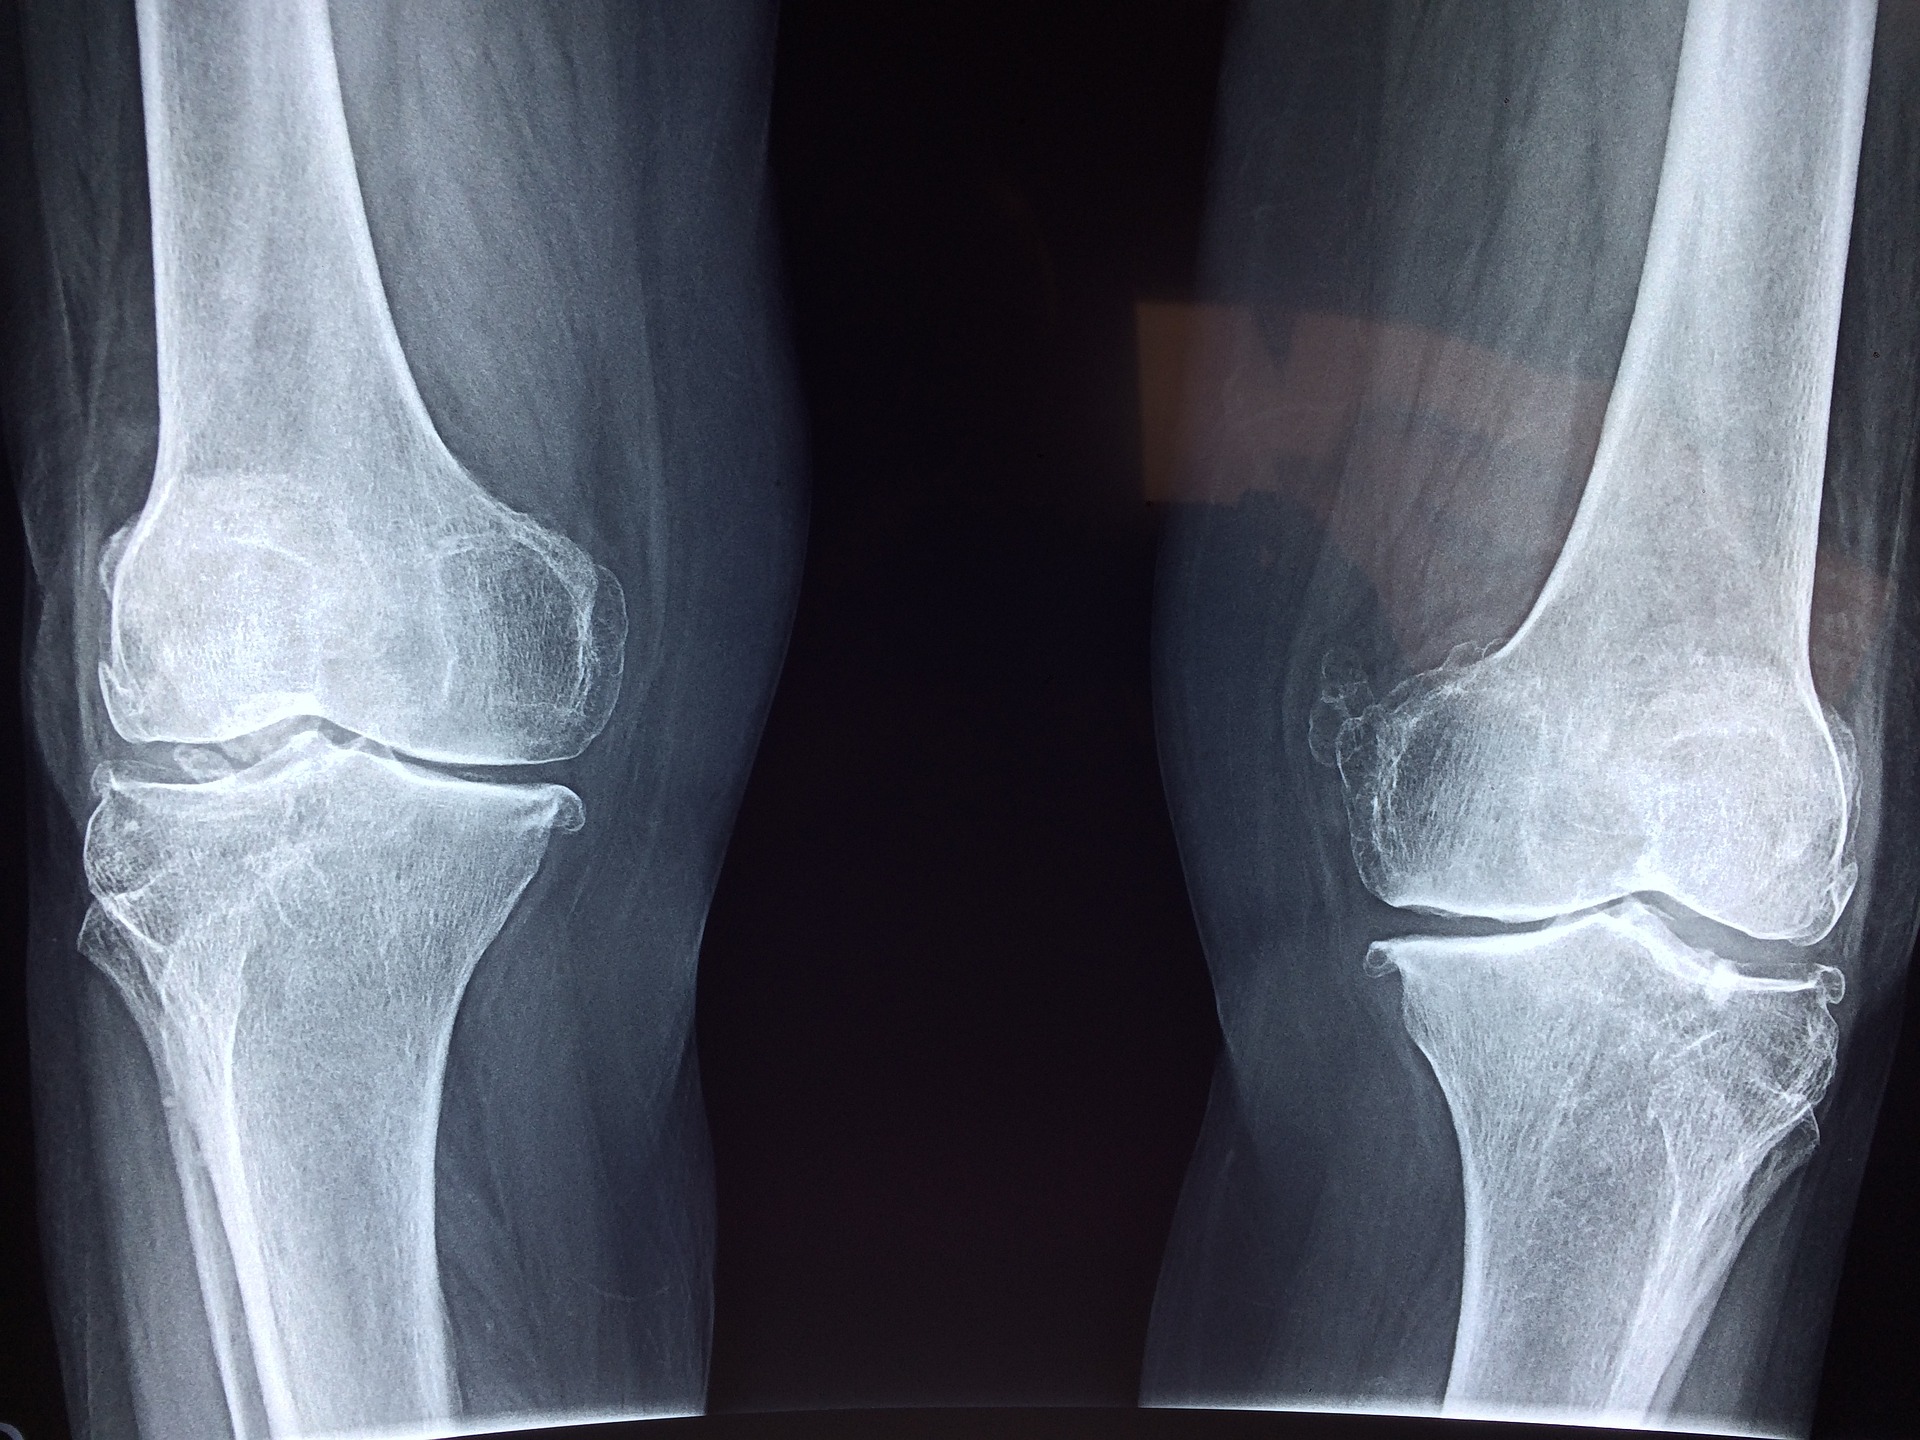

퇴행성 관절염은 관절의 연골이 점차 소모되면서 염증과 통증이 발생하는 마모성 비염증성 질환으로 겨울철 잘 나타납니다. 보통 노화에 따라 자연스럽게 발생할 확률이 높지만 체중이 많이 나가거나 과격한 운동으로 관절에 계속 무리를 받게 되면 퇴행성 관절염의 발병을 앞당길 수 있습니다. 유전적인 요인에 의해서도 퇴행성 관절염에 걸릴 확률이 높아질 수 있으므로 이에 대한 건강관리 및 조치가 필요합니다.

2. 퇴행성 관절염 증상

퇴행성 관절염 증상은 천천히 발생하고 알게 모르게 증상이 악화될 수 있으므로 다음과 같은 증상이 조금이라도 나타난다면 의심해봐야 합니다. 수면 중이나 일상생활, 운동 중이나 운동 후 통증으로 통증이 계속된다면 퇴행성 관절염이 악화되고 있다는 신호일 수 있습니다. 관절염 관절 주변 근육이 약화되거나 붓기가 생기고 압통이 느껴지거나 뻣뻣함이 지속된다면 퇴행성 관절염의 증상으로 볼 수 있습니다. 갈라지고 삐걱거리는 소리가 난다면 가까운 정형외과를 찾으시길 추천드립니다.